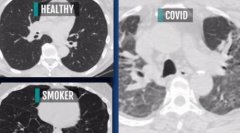

智能网[http://www.znw.com.cn/]消息,现在有一些人在担心人工智能的发展对人类的影响会走向何方。但是在现阶段人工智能的发展比如说自动驾驶,语音识别,还有帮助医生来对医学图像的判断这方面都已经发挥了很重要的作用。

中国科学院院长白春礼在访问莫斯科结束时的新闻发布会上接受俄罗斯卫星通讯社采访时对中国的科技进步进行评论称,现在有一些人在担心人工智能的发展对人类的影响会走向何方。但是现阶段人工智能的发展,比如说自动驾驶、语音识别、还有帮助医生来对医学图像作出判断这方面都已经起到了很重要的作用。

白春礼说:”像美国的阿尔法go通过把棋谱记下来之后,再通过大数据的分析可以战胜人类。但是第二代的阿尔法Alpha Go Zero就可以自己跟自己对弈,自己来学习。所以说人工智能的发展是人工智能的算法起到非常重要的作用。现在的人工智能还没有达到真正的去理解的这个程度。现在也有一些人在担心人工智能的发展对人类的影响会走向何方。但是在现阶段我觉得人工智能的发展比如说自动驾驶,语音识别,还有帮助医生来对医学图像的判断这方面都已经发挥了很重要的作用。但是要避免人工智能可能会给人类带来负面的影响,关键是我们在发展新技术的过程当中,要从前期的立法角度上来避免一些可能的负面影响,这个很重要。”

888大奖88pt88:研究:新冠患者肺部伤疤比吸烟严重02-04

888大奖88pt88:研究:新冠患者肺部伤疤比吸烟严重02-04 -